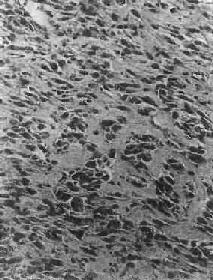

镜下观,肿的分化程度差异很大,分化好的软骨肉在镜下易误诊为软骨,但在肿的边缘可以找到细胞的异型性,如核肥大、深染,出现较多的双核、巨核和多核巨细胞,并可见明显核仁(图17-4)。在分化差的软骨肉则上述细胞的异型性很明显,核分裂像也多见。软骨肉的基质可为与一般透明软骨相似的透明基质,也可为粘液样基质,常见于恶性程度高的软骨肉

软骨肉<a href=瘤"/>

图17-4 软骨肉

软骨细胞大小不等,有的较大。许多细胞有肥硕的胞核,有的有双核